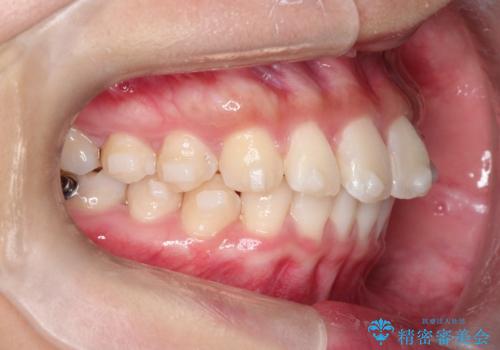

【インビザライン】翼状捻転+出っ歯を治したい

- 前歯の捻れと口元の突出を主訴に来院されました。

インビザラインを用いて上顎の遠心移動を行い、前歯を下げながら凸凹を綺麗に治すことができました。

歯を抜かない矯正治療を行う場合、口元は極端には変わりません。

今回は奥歯の遠心移動を行い、できる限り前歯を下げられるように治療を行いました。